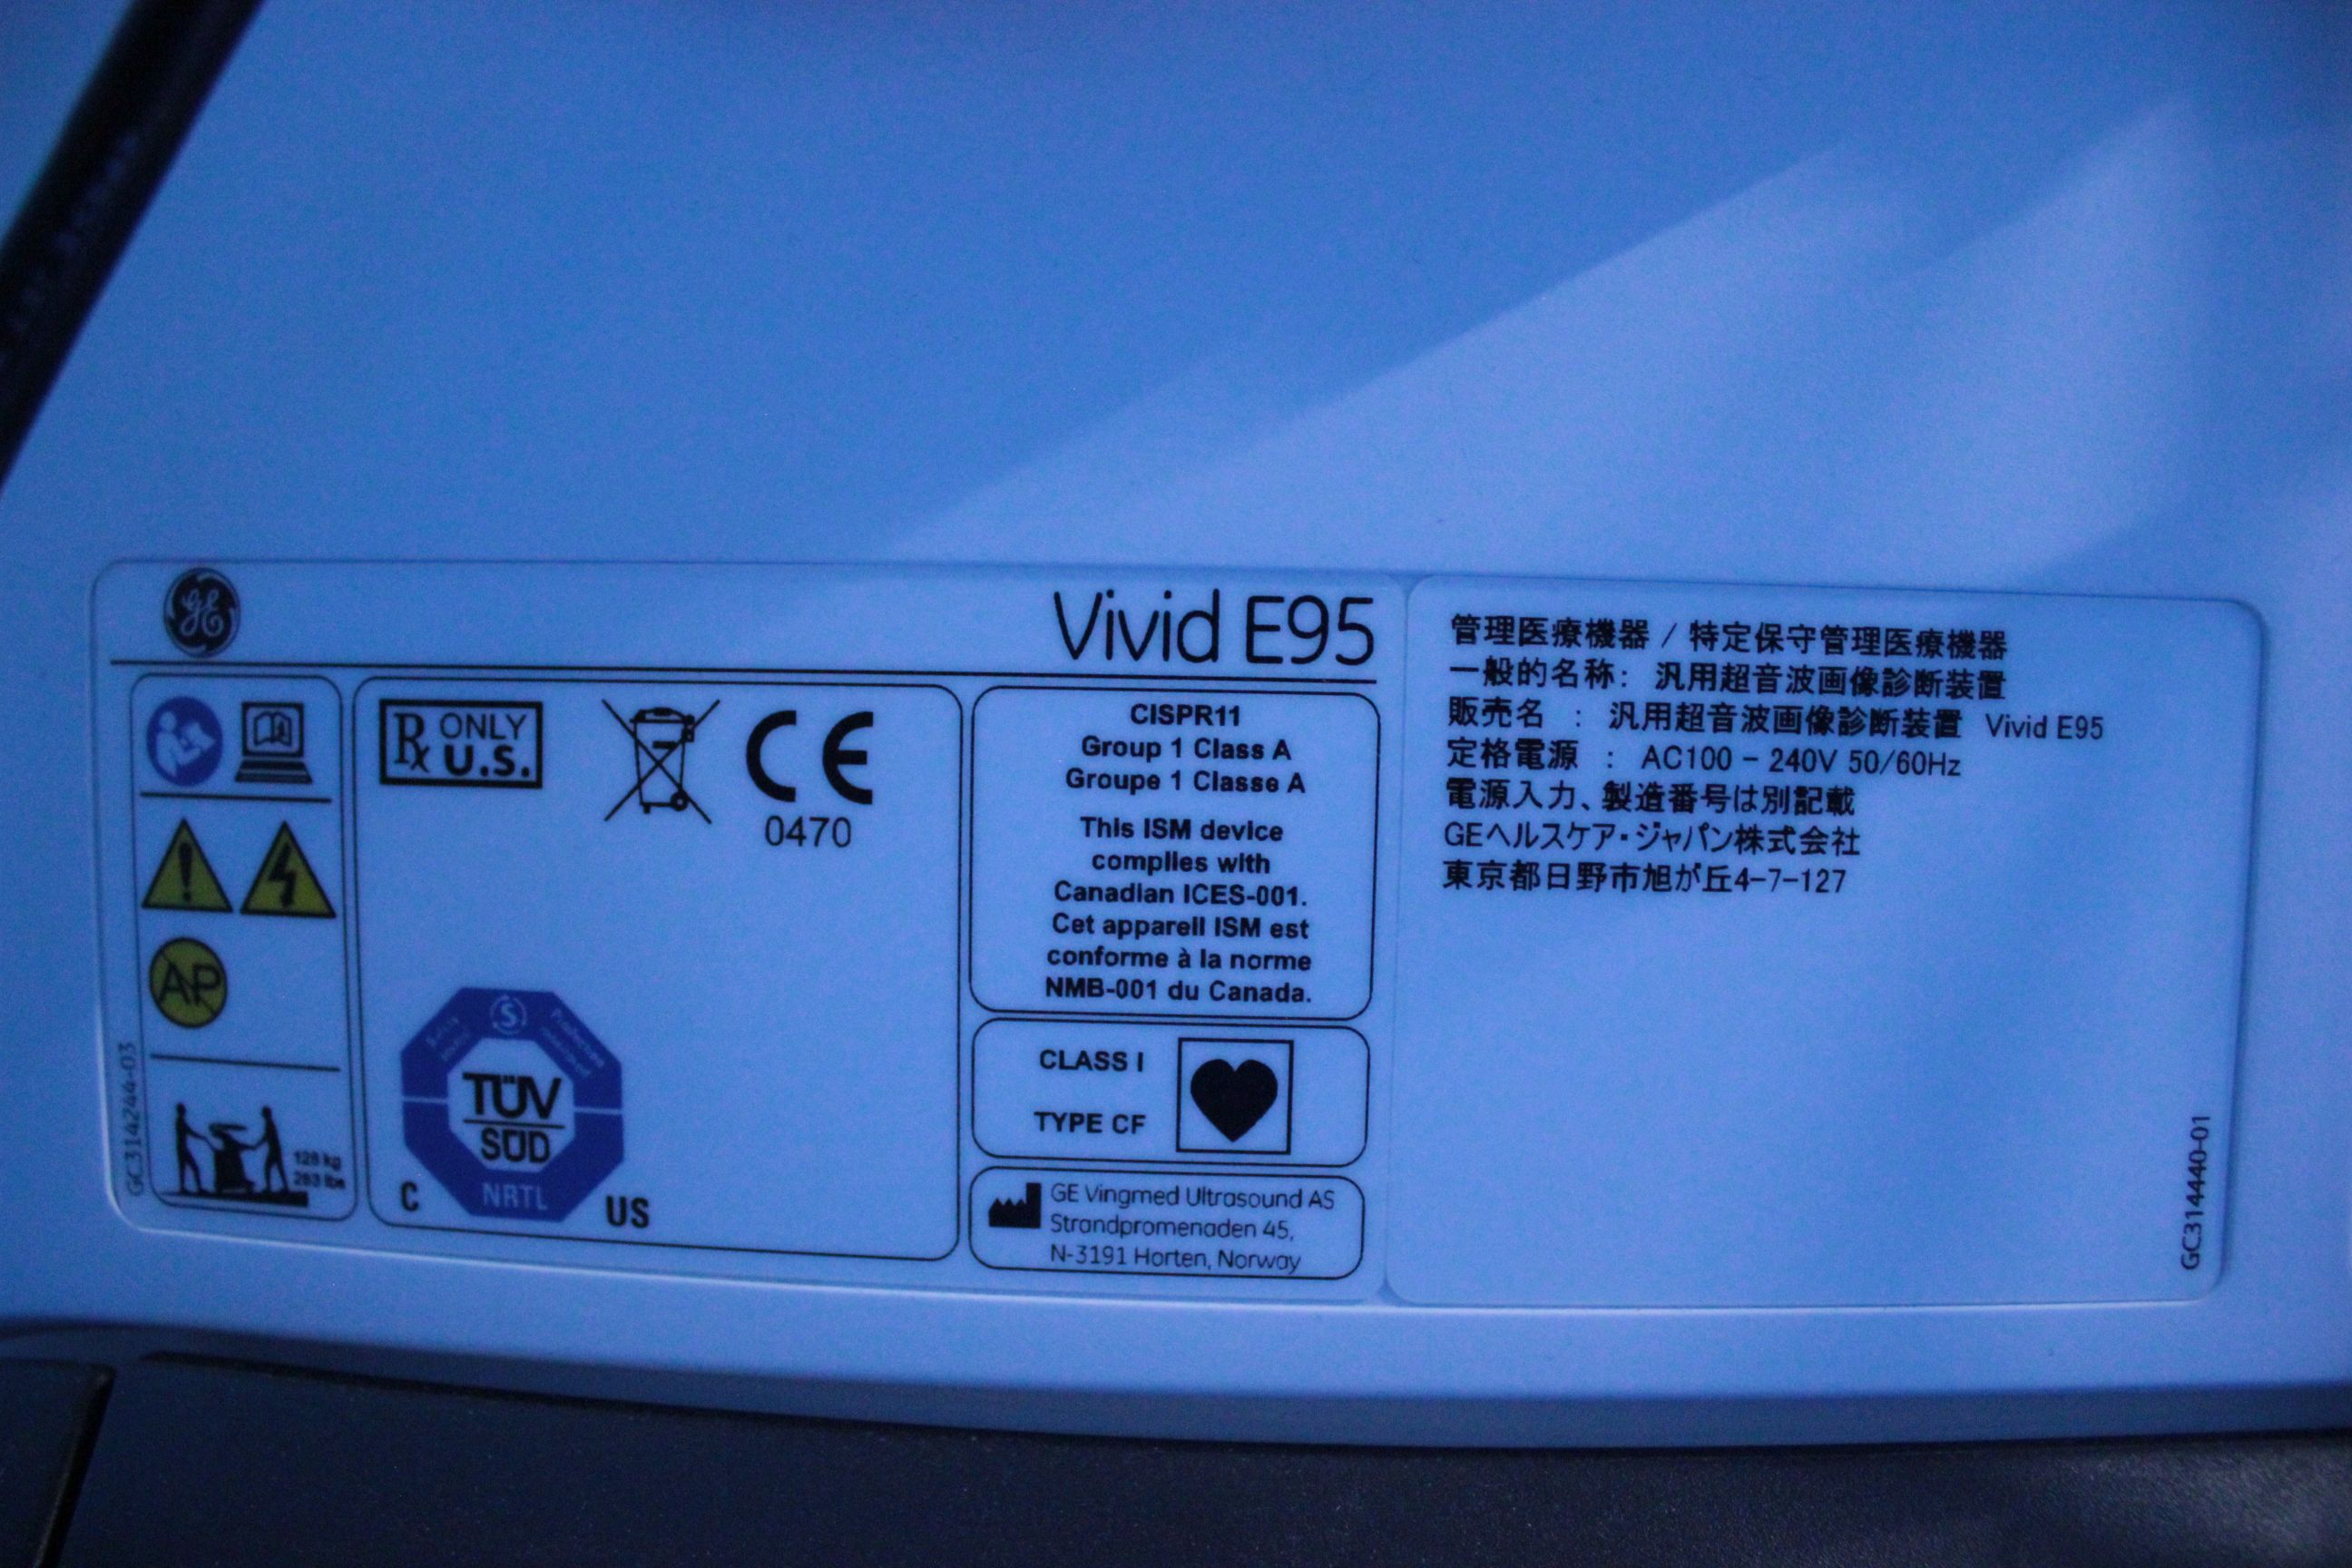

超音波検査 | これまさクリニック 府中市是政 是政駅 内科 消化,![超音波診断装置|GEヘルスケア|PRODUCT_CODE]|中古医療機器の 超音波診断装置|GEヘルスケア|PRODUCT_CODE]|中古医療機器の](https://www.quon-healthcare.com/contents/lot/2/10_0000013313_2_0_cLNIqh.jpg) 超音波診断装置|GEヘルスケア|PRODUCT_CODE]|中古医療機器の,

超音波診断装置|GEヘルスケア|PRODUCT_CODE]|中古医療機器の, 在庫情報|中古医療機器のジャパンセントラルメディカル,

旭川医科大学 臨床シミュレーションセンター, 商品詳細|11481|GEヘルスケアジャパン|超音波診断装置|Vivid,

商品詳細|11481|GEヘルスケアジャパン|超音波診断装置|Vivid, 超音波検査 - 画像部門(放射線) - 診療科・部門案内 | 大垣,

超音波検査 - 画像部門(放射線) - 診療科・部門案内 | 大垣, 商品詳細|11481|GEヘルスケアジャパン|超音波診断装置|Vivid,

商品詳細|11481|GEヘルスケアジャパン|超音波診断装置|Vivid, 楽天市場】腹部エコー 超の通販,